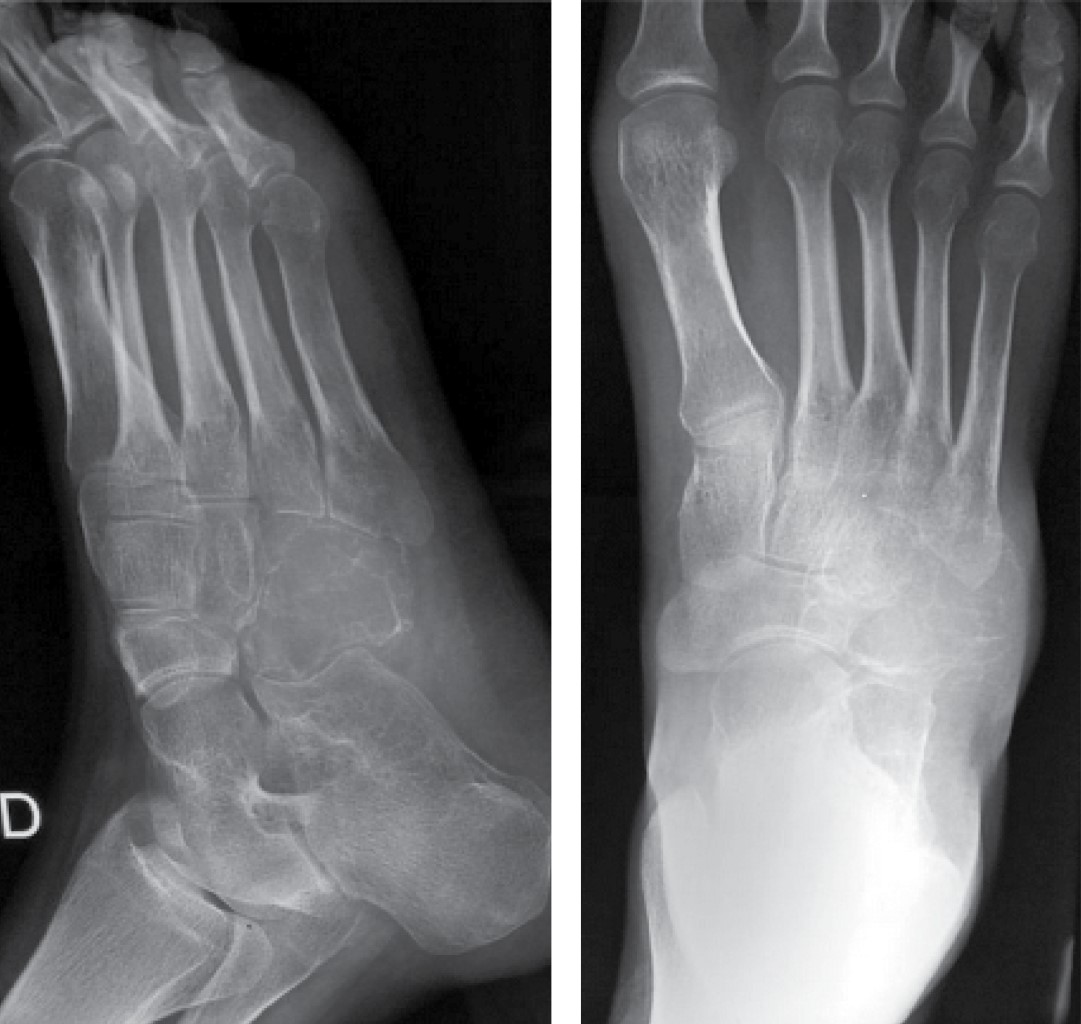

Aggressive chondroblastoma of the cuboid, unusual location. Case report and literature review

The case of a cuboid chondroblastoma in a 15-year-old woman is presented. This tumor presents an aggressive behavior which does not respond to treatment by curettage, bone grafting and adjuvant cryosurgery in the tissues affected by the tumor. The torpid evolution subsequently forces the need of a radical resection. Despite being classified as an aggressive benign tumor, a mention is made of the possibility of pulmonary metastases and local aggressiveness in some cases, such as that of this patient.

Figure 1

Figure 2